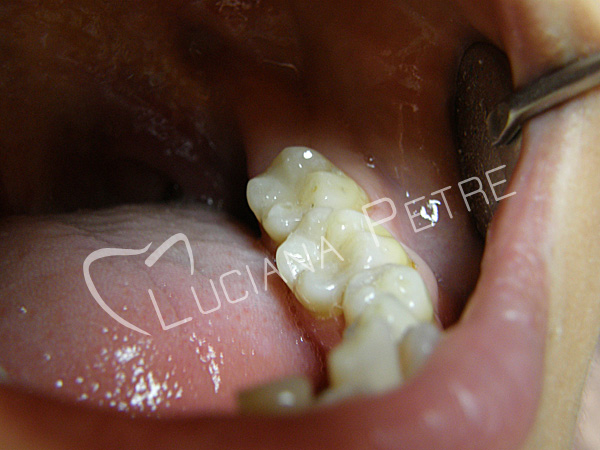

Carii pe molari

Obturatii fizionomice